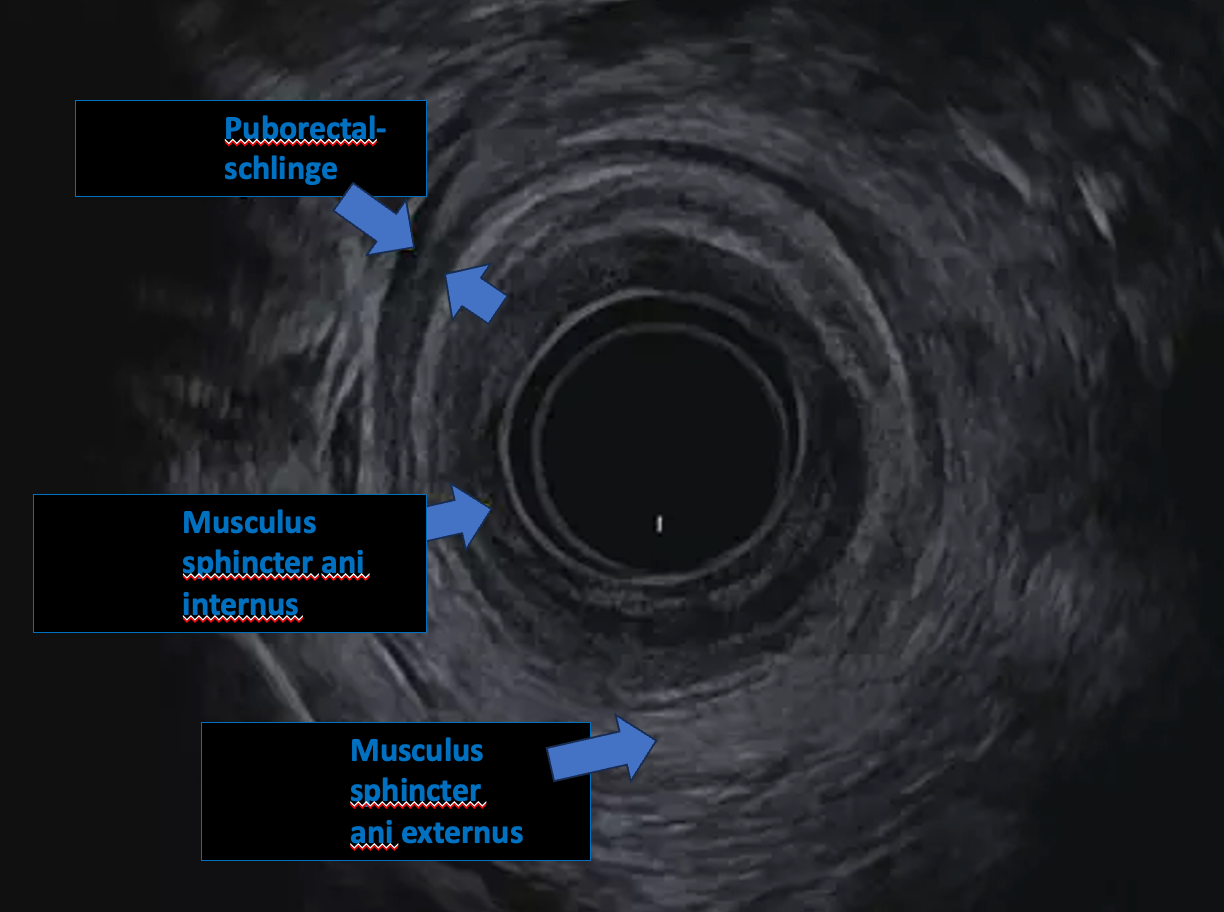

• Untere / rektale Endosonographie: über den After (v. a. Mastdarm/Enddarm, z. B. bei Tumorabklärung, Fisteln, Abszessen).

• Rektale Fragestellungen: z. B. Fisteln, Abszesse, Tumoren; Beurteilung der Eindringtiefe hilft bei der Therapieplanung.